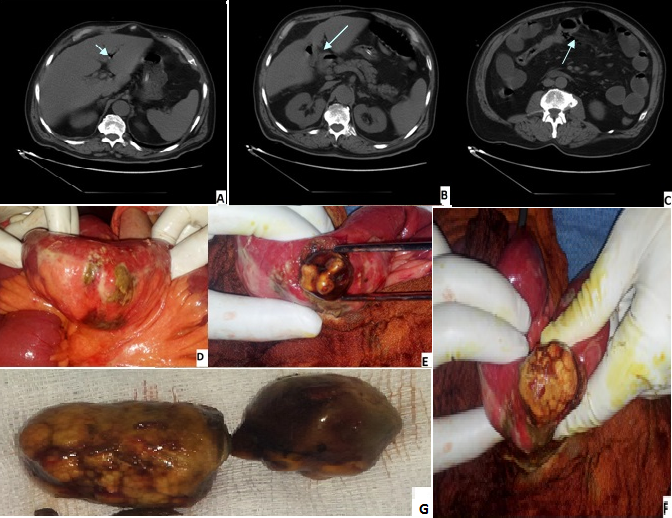

L'iléus biliaire est une complication rare de la lithiase biliaire; il est caractérisé par la triade radiologique, syndrome occlusif, aérobilie et localisation ectopique d'un calcul dans le tube digestif. La cause est généralement une fistule cholécysto-duodénale. L'enclavement de calcul au niveau d'une anse qui est généralement la dernière anse iléale peut se compliquer d'une perforation grêlique. Nous rapportons le cas d'un patient de 72 ans, admis pour syndrome subocclusif remontant à une semaine, chez qui l'examen clinique trouve un patient fébrile à 37,8 °C avec une défense péri-ombilicale et épigastrique avec au bilan biologique une CRP à 320 et GB=8000 elt/mm3 et une insuffisance rénale d'allure fonctionnelle. Un ASP a montré des niveaux hydro aériques gêliques et une TDM abdominale - a mis en évidence une aérobilie avec une fistule cholécysto-duodénale associée à pneumopéritoine. L'exploration chirurgicale confirme la présence de la fistule cholécysto-duodénale et objective la présence de deux calcules cholestéroliques au niveau de la lumière intestinale avec une perforation grélique à 1m20 de l'angle de treitz. Le geste chirurgicale a consisté en une résection d'environ 10 cm de grêle emportant la perforation avec extraction de deux gros calcules de 4 et 3 cm de grand axe et transformation des deux bouts grêliques en une stomie à la Bouillie-Wolkman sur le flanc gauche et à un lavage et drainage et nous avons décidé de ne pas libérer la fistule cholécysto-duodénale et de la traiter ultérieurement. Les suites post opératoire immédiates ont été simples.